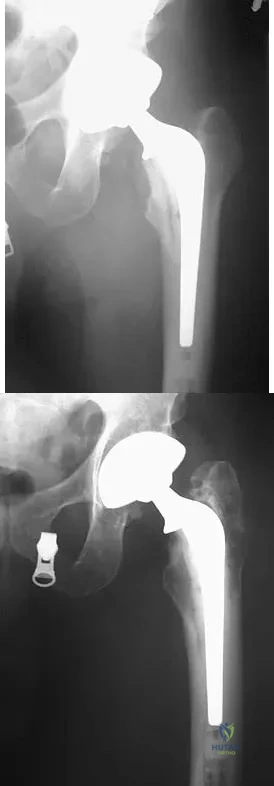

What complication is most likely to develop after right total hip arthroplasty in the patient shown in Figure 5?

Explanation